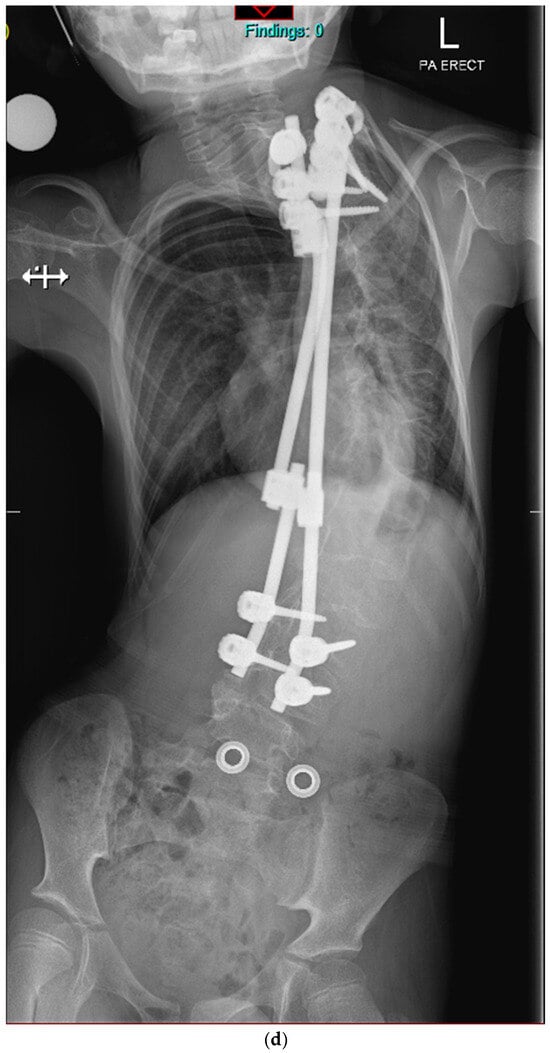

Previously Unreported TMEM38B Variant in Osteogenesis Imperfecta Type XIV: A Case Report and Systematic Review of the Literature

Osteogenesis imperfecta (OI) type XIV is a rare recessive disorder caused by TMEM38B pathogenic variants that disrupt an endoplasmic reticulum protein essential for calcium homeostasis and bone mineralization. This leads to severe bone fragility, early-onset fractures, skeletal deformities, low bone mass, scoliosis, and [...] Read more.

Osteogenesis imperfecta (OI) type XIV is a rare recessive disorder caused by TMEM38B pathogenic variants that disrupt an endoplasmic reticulum protein essential for calcium homeostasis and bone mineralization. This leads to severe bone fragility, early-onset fractures, skeletal deformities, low bone mass, scoliosis, and variable features like blue sclerae or dental abnormalities. We present a case report of a 21-year-old Italian male with a novel homozygous TMEM38B splice variant (c.112 + 1G > T), detailing the clinical presentation, genetic findings, and therapeutic outcomes. The patient exhibited multiple skeletal deformities and showed a moderate response to bisphosphonate therapy (neridronate). In addition, a systematic review of PubMed and Scopus identified 12 relevant studies from an initial set of 82 publications, encompassing data from 56 patients diagnosed with OI type XIV. Unlike classical collagen-related OI, TMEM38B-related OI necessitates genetic screening beyond classical collagen genes (COL1A1 and COL1A2). While bisphosphonates provide some clinical benefit, persistent fractures underscore the need for long-term management and innovative therapies. This case report and systematic review enhance understanding of OI type XIV and underscore the clinical importance of TMEM38B variants in bone fragility disorders. Full article